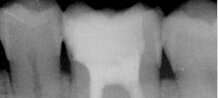

FICHE CLINIQUE Prothèse fixée conventionnelle : Couronnes et bridges